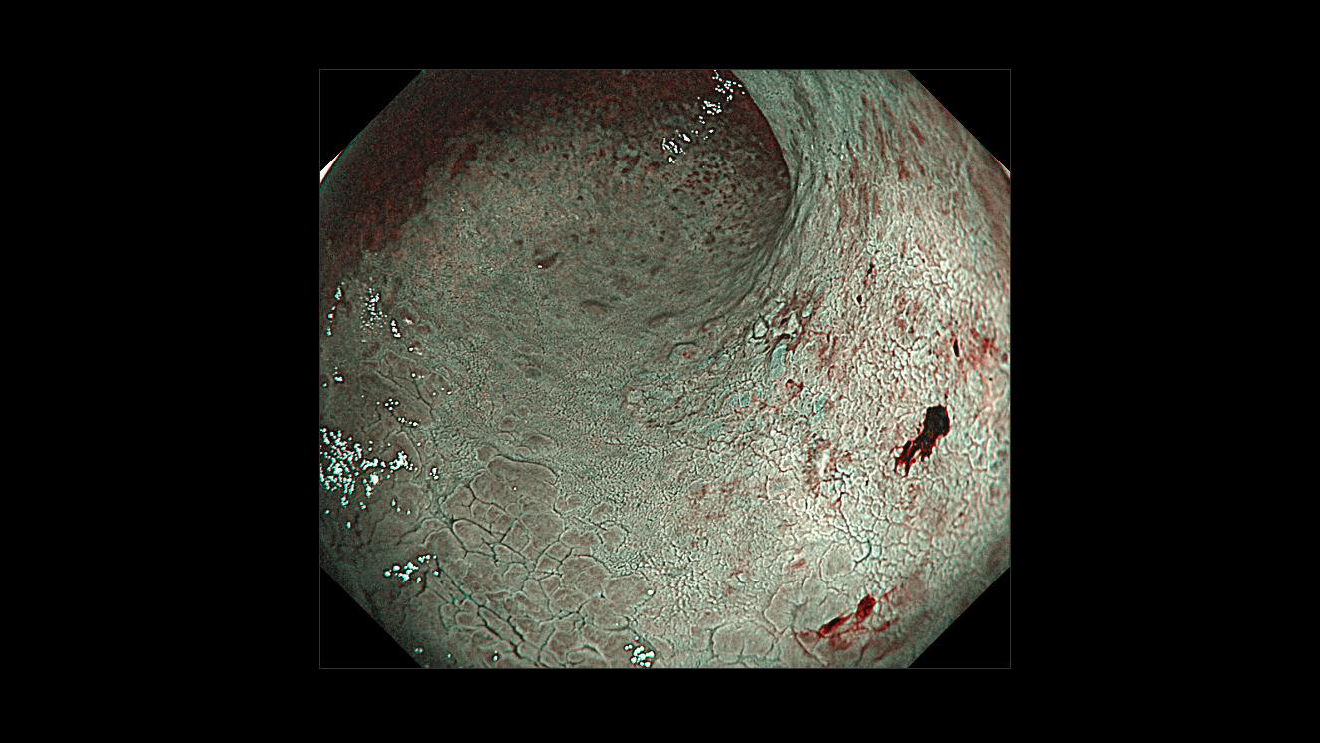

ホーム > 診療科・部門案内 > 消化器センター 消化器内科 > 消化管Mapping > 消化管Mapping~胃~ > 消化管Mapping~胃~ 2025.9.10